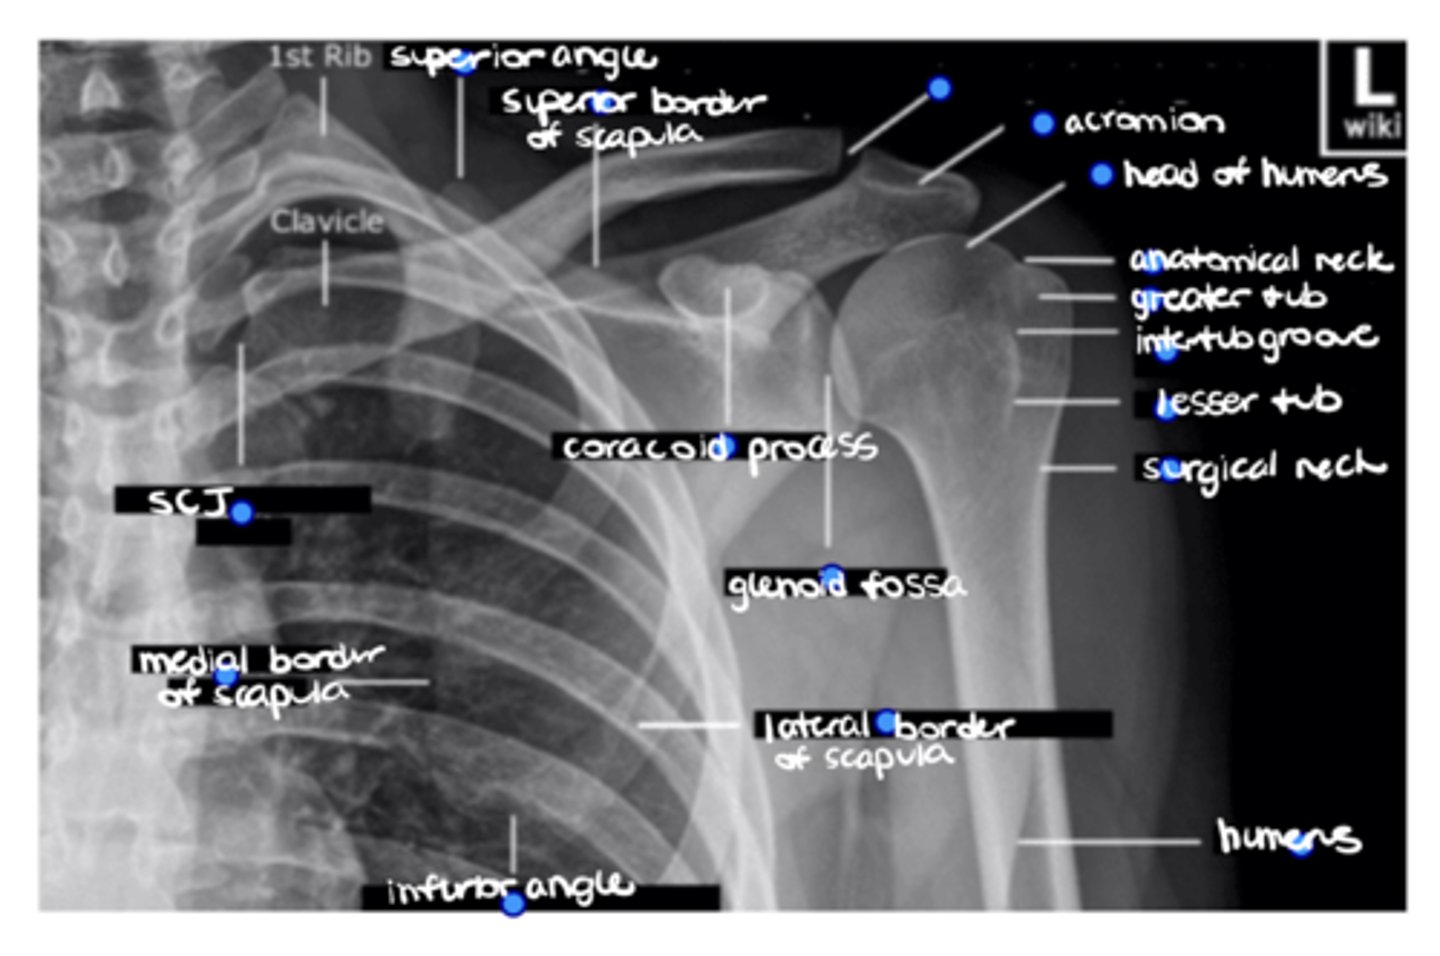

Superior angle of the scapula

ID the missing structure.

Superior border of the scapula

ACJ

Acromion

1. Head of humerus

2. Anatomical neck

3. Greater tuberosity

4. Intertubercular groove

5. Lesser tuberosity

6. Surgical neck

ID the 6 missing structures.

Shaft of the humerus

1. Coracoid process

2. Glenoid fossa

ID the 2 missing structures.

1. Lateral border of the scapula

2. Inferior angle of the scapula

3. Medial border of the scapula

ID the 3 missing structures.

SCJ